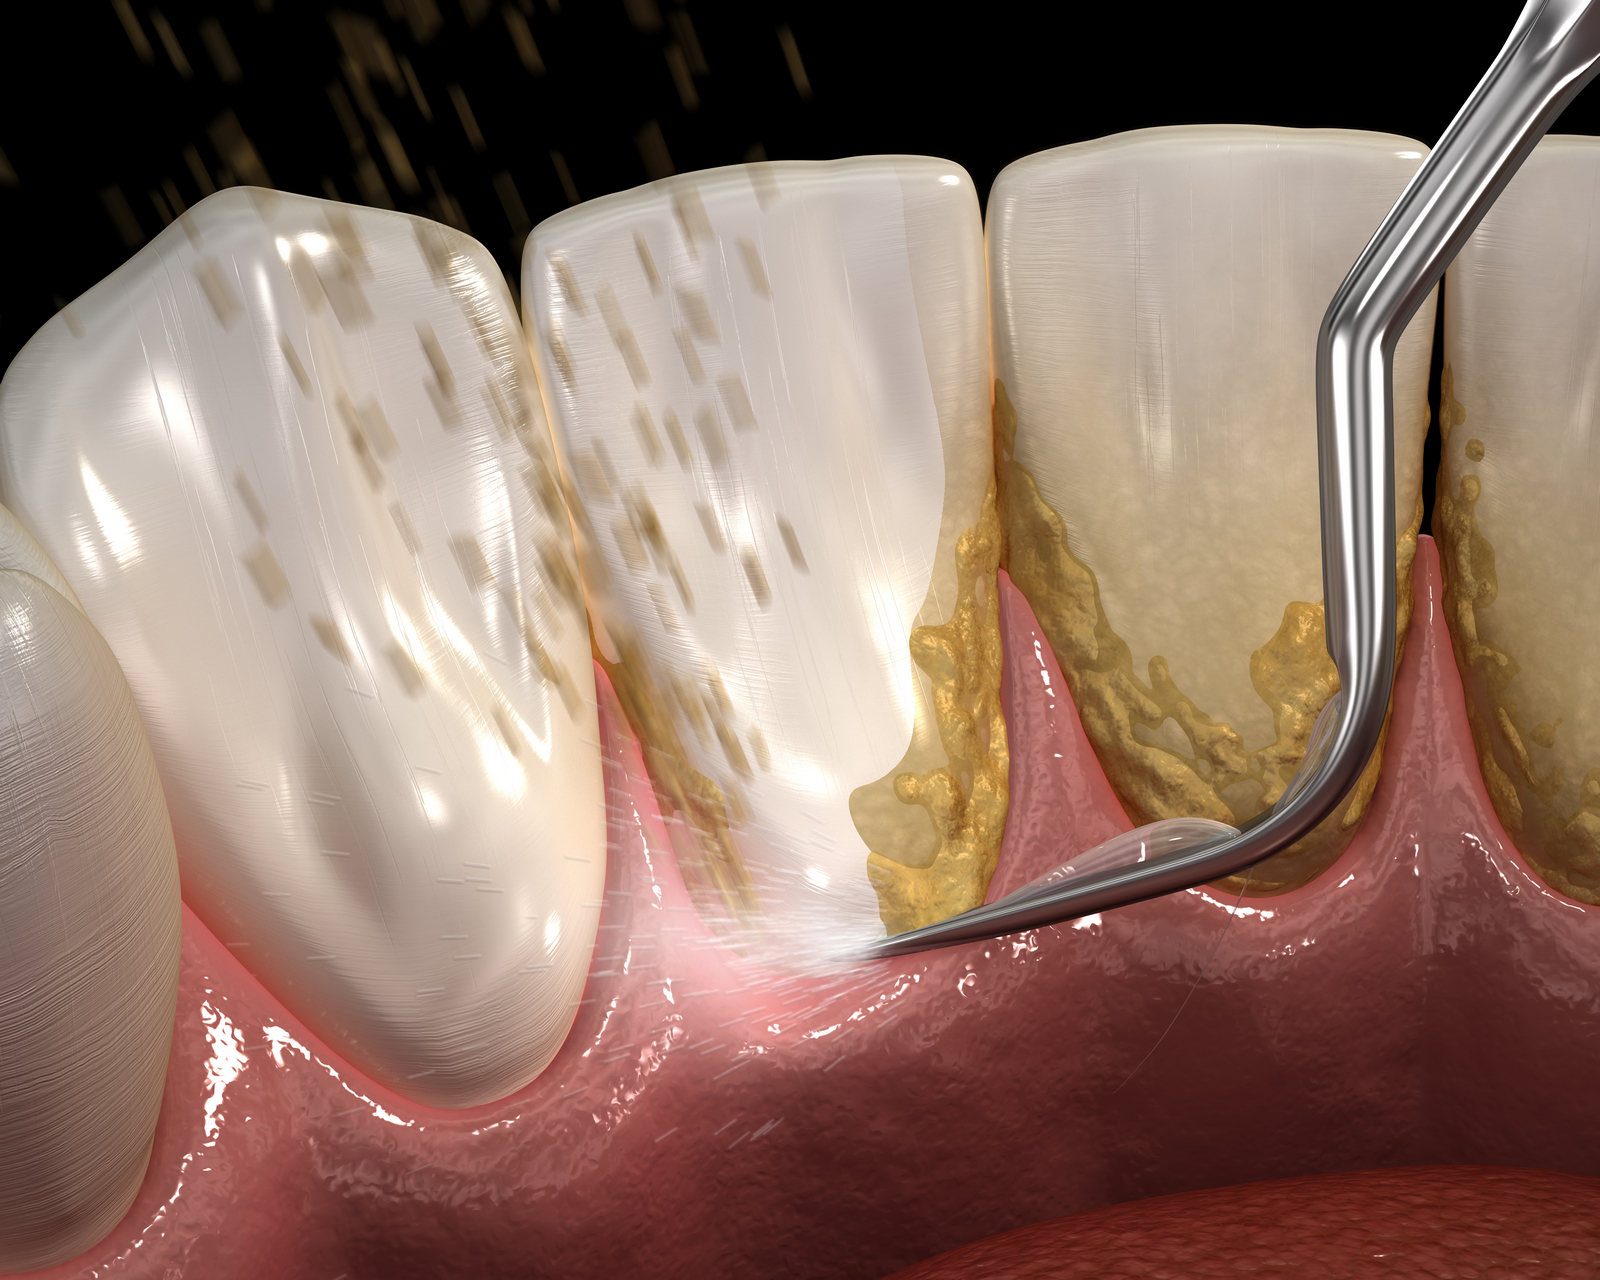

Placa bacteriană este o peliculă subțire care se formează continuu la baza dinților și este formată în principal din particule alimentare, salivă și bacterii, având o textură moale și o culoarea albicioasă, uneori chiar gălbuie. Aceasta încorporează constant materiile anorganice din salivă , în principal sărurile de calciu. Astfel, placa bacteriană se transformă, în timp, dintr-un depozit moale, într-un depozit dur numit tartru dentar.

Tartrul acționează ca un mic țep iritativ pentru gingii determinând sângerare gingivală, inflamație și retractie gingivală. Fiind un depozit ce stă pe suprafața dentară poate masca cariile deja existente, oferindu-le un mediu propice pentru dezvoltare. Din păcate, tartrul nu poate fi îndepărtat prin regimul obișnuit de igienă orală la domiciliu, ci se tratează doar prin profilaxie profesională, realizată în cabinetul stomatologic.

- Detartrajul – este o metodă simplă, rapidă și non – invazivă ( nu afectează structura dintelui, nu zgârie smalțul) de îndepărtare a depozitelor de placă bacteriană și de tartru dentar de pe toate suprafețele dentare, inclusiv interdentar. Se realizează folosind un dispozitiv cu ultrasunete, răcind dintele cu un jet de apă pentru a evita apariția durerii. Această procedură va elimina acumulările care cauzează mobilitatea dinților în timp și apariția bolii parodontale.